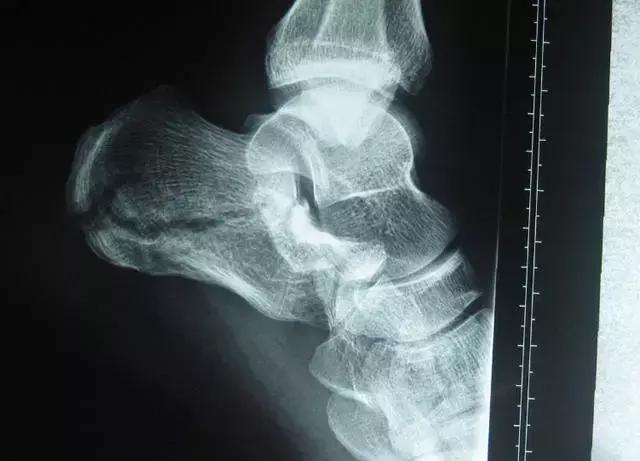

(2)跟骨骨折

对于正常人来说,跟骨是不容易骨折的。但若从高处坠落,或骨质流失严重人群的跟骨的确易骨折。若脚后跟疼痛的同时,还出现肿胀、皮肤淤紫甚至不能行走的情况,这种可能性很大。

此时要立即到骨科就诊。医生会通过X片等检查明确是不是骨折,如果确实有骨折,就需要石膏固定或者手术治疗。